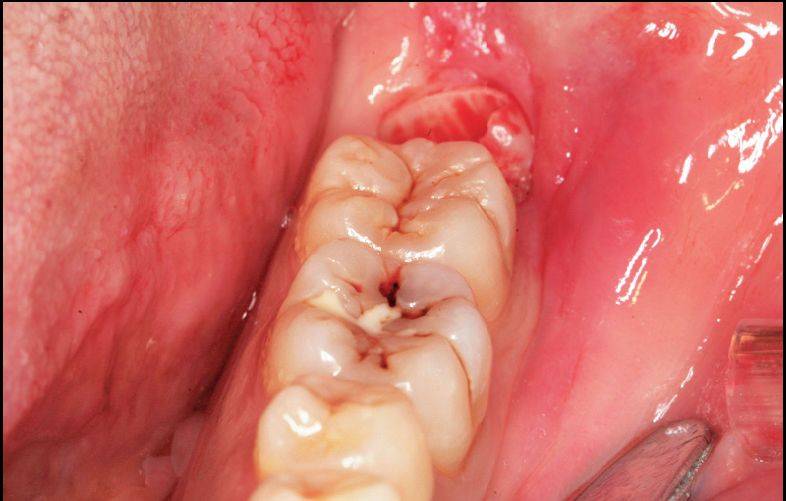

A.水平智齿仅露出远中牙冠

C.直接分牙法并未切开、翻瓣、去骨拔除

D.智齿拔除,牙槽窝完好

同样的阻生智齿的不同拔除方法